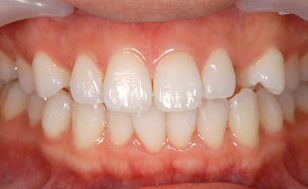

前歯のセラミック症例

| 主訴 | 前歯の色が変色していることが気になる。 (オールセラミック) |

| 年齢・性別 | 30代 男性 |

| 治療期間 | 約3週間 |

| 治療内容 | オールセラミック |

| 治療本数 | 1本 |

| 治療費用 | 仮歯(テック)5,500円(税込) +かぶせ物代 (オールセラミック)110,000円(税込) |

| 治療方針 | ①歯の形態、かみ合わせ等を模型上で 診査、患者さまと相談した上で形態の決定 ②仮歯の装着 ③セラミックの試適(色・形の確認) ④セラミック装着 |

| ドクターのコメント | 治療後はセラミック治療による審美性は 獲得できましたが術前と比べ、 ホワイトニング後の後戻りがあり、 歯が黄ばんできているので、 ホワイトニング後のメンテナンスの 重要性をお伝え致しました。 |